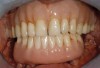

Fig 8. Failing dentition in an 82-year-old patient currently diagnosed with tardive dyskensia.

Figure 8

Fig 9. Transition line could not be hidden due to uncontrolled contortions of the facial musculature.

Figure 9

Fig 10. Recording a repeatable centric position was virtually impossible for this patient due to spasticity of the masticatory system. Among the compromises necessary in creating an occlusal scheme was to revert to a monoplane approach.

Figure 10

Fig 11. Recording a repeatable centric position was virtually impossible for this patient due to spasticity of the masticatory system. Among the compromises necessary in creating an occlusal scheme was to revert to a monoplane approach.

Figure 11

A patient with tardive dyskensia, for example, may experience dramatic changes in expressive facial activity and corresponding dysfunction in the muscle memory needed to repeat a centric position.19,20 Figure 8 and Figure 9 show an 82-year-old patient who had previously been treated for depression, had a failing dentition, and was diagnosed with tardive dyskensia. Extreme uncontrolled contortions of the facial musculature were evident in the patient when attempting to record a high smile line; removal of enough maxillary bone to hide the transition line was impossible. Dramatic compromises in occlusal scheme may be necessary to achieve even a moderately successful result; yet the implant approach realistically may be the only way to offer any functional improvement (Figure 10 and Figure 11).